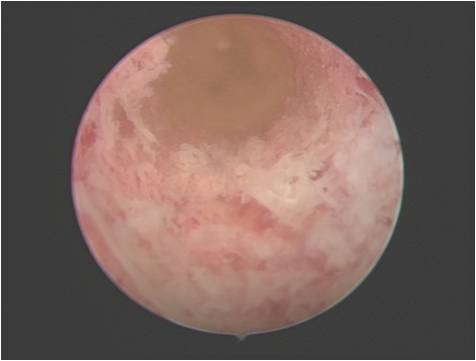

半月板缝合